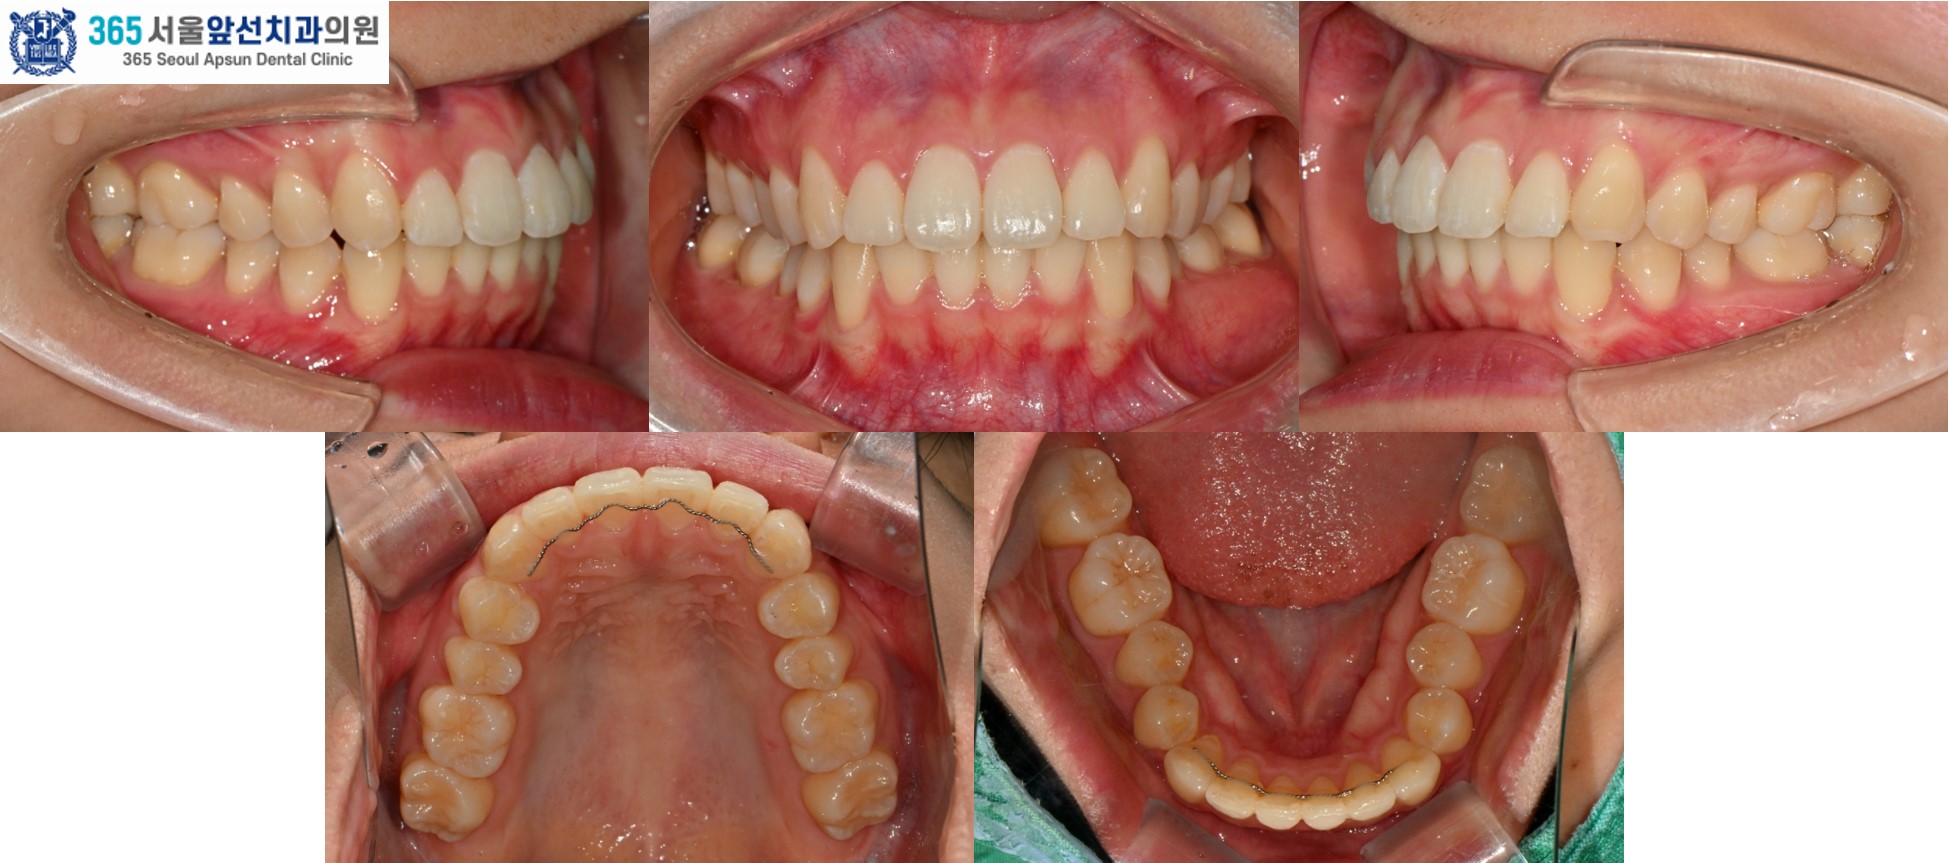

(그림1) 촬영일자 2025.02.25. / 2025.11.06.

치료 후의 모습입니다. 아랫니 치열은 약 5개월, 윗니 치열은 약 7개월의 치료기간이 소요되었습니다. 앞니의 치열이 가지런하게 배열되어 환자분도 만족하셨습니다. 미소 시 자연스럽고 단정한 인상으로 변화하였습니다. 앞니 부분 교정 증례의 치료기간은 4-9개월 사이로 정도에 따라 상이합니다. 부분 교정 관심 있으신 환자분들께서는 365서울앞선치과로 내원하셔서 교정 진단 받아보시길 바랍니다. 감사합니다!